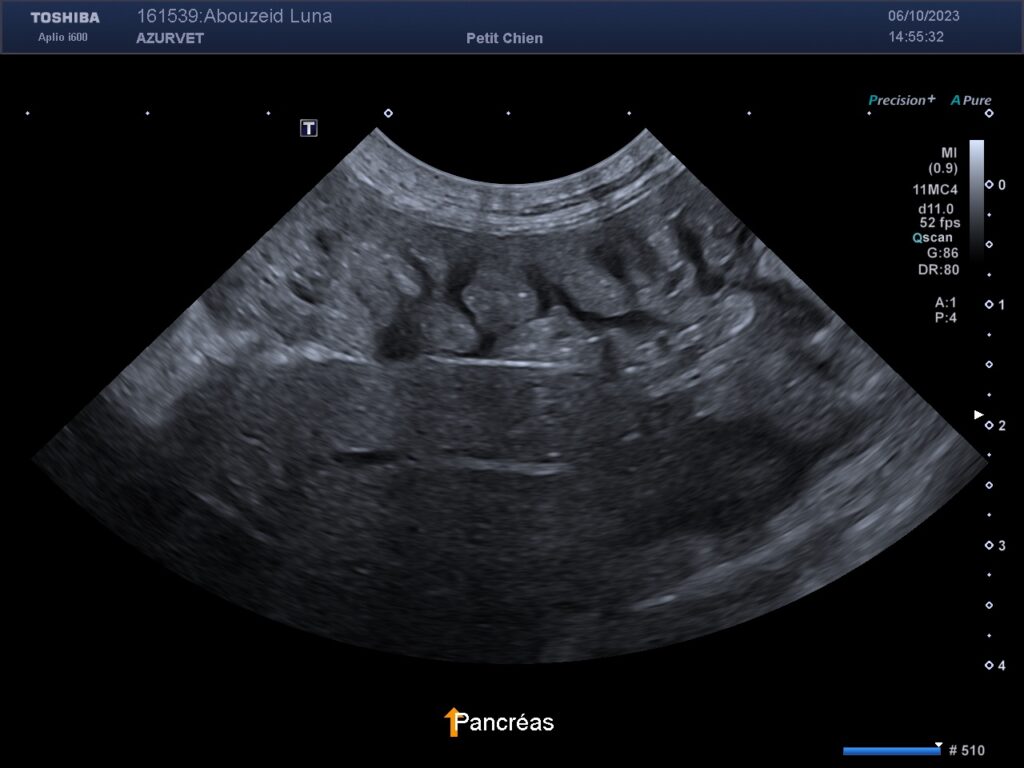

2) Un épaississement avec aspect zébré du pancréas (travées hypoéchogènes lunéaires) lié à un oedème (secondaire à l’hypoalbuminémie) : figure 3 ci-dessous.

Figure 3 : échographie du pancréas d’un Cairn de 9 ans souffrant de lymphiectasie avec épaississement et aspect zébré du pancréas.